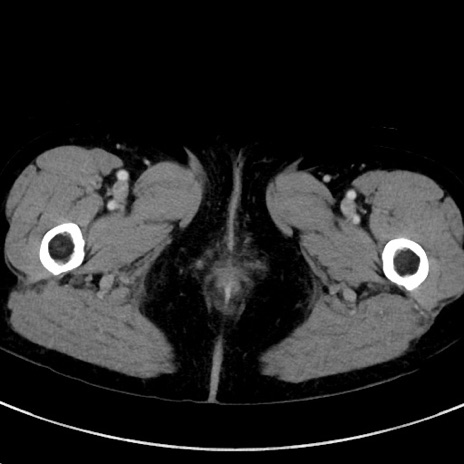

症例23(横断像)

【症例】70歳代女性

【主訴】下腹部痛・嘔吐

【現病歴】2日前より腹痛あり。昨日嘔吐あり。症状改善しないため来院。

【既往歴】胃GISTに対して胃部分切除後。

【身体所見】BT 37.1℃、BP 128/77mmHg、腹部:平坦・軟、下腹部に圧痛あり。

【データ】WBC 10200、CRP 0.31